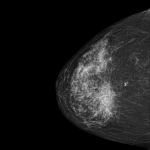

Uma das principais áreas onde a IA tem mostrado grande promessa é no diagnóstico médico. Algoritmos de IA podem analisar grandes volumes de dados, incluindo imagens de exames como tomografias, ressonâncias magnéticas e radiografias, para identificar padrões sutis que podem escapar à detecção humana. Isso pode levar a diagnósticos mais precisos e rápidos, permitindo um tratamento mais eficaz e precoce.

Na imagem abaixo podemos ver como é uma leitura realizada por IA de um exame de mamografia de uma paciente com câncer de mama.